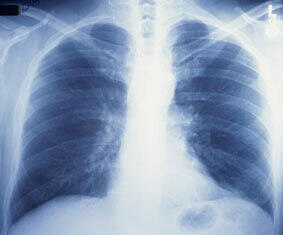

Des chercheurs du Children's Hospital & Research Center d'Oakland, en Californie, ont testé l'effet de la vitamine C comme agent de traitement complémentaire de l'asthme, de la mucoviscidose et du syndrome respiratoire obstructif. Ils ont examiné son action sur une protéine appelée régulateur de la conductance transmembranaire de la mucoviscidose (CFTR, cystic fibrosis transmembrane conductance regulator) qui régule les sécrétions de fluide dans les parois des voies respiratoires. |

La vitamine C induit une ouverture des canaux du CFTR et une meilleure exposition des parois des voies respiratoires à la vitamine C qui stimule la production de fluide. Les chercheurs ont dit que la vitamine C favorise une hydratation normale des parois des voies respiratoires et que des déficiences en vitamine C pourraient conduire à l'adhésion du mucus sur les membranes tapissant les voies respiratoires. |